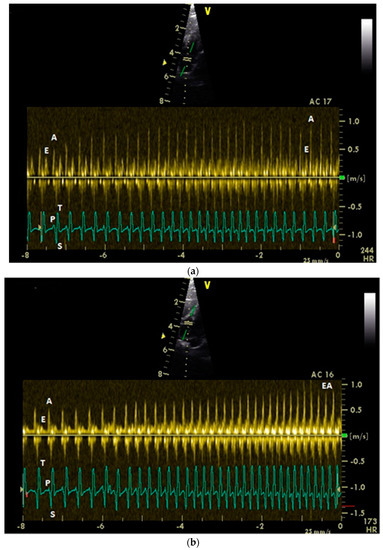

3.2. Influence of Isoflurane Anesthesia on Diastolic Blood Flow Velocities

3.4. Examination of the Diastolic Blood Flow with Color Doppler Flow Imaging